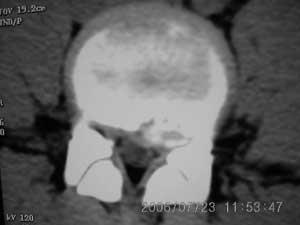

以下是引用xiaoniu在2006-7-23 12:47:00的发言:[br]椎体后缘软骨结节[br]【发病机制】尚未完全清楚,存在多种学说。一般认为青少年时期,脊柱负重压力及髓核膨胀性压力下,椎间盘组织通过椎体薄弱区疝入椎体内,局部骨小梁吸收被椎间盘组织代替形成软骨结节,周围骨小梁出现反应性硬化,逐渐形成骨壳包绕软骨结节。 椎体后缘软骨结节是椎间盘组织向后疝入椎体后缘的结果,为边缘性软骨结节的一种特殊类型。[br]【ct表现】椎体后缘类圆形、多囊状或不规则形的骨质缺损区,大小不一,位于椎体后缘正中或偏侧,其ct值等同于同层面的椎间盘,70~90hu,边界清楚,常有薄厚不一的硬化带。缺损区后方骨块突入椎管内,椎管狭窄,硬膜囊受压。[br]【鉴别诊断】本病诊断不难,需与以下疾病鉴别[br] 1 椎间盘突出钙化。2 后纵韧带骨化。3退变形成的骨赘。4锥体后缘撕裂性骨折。[br]上述疾病骨块影的形态及位置均各具特征,且椎体后缘均无低密度的骨结软节,鉴别不难。[br][br][本贴已被 xiaoniu 于 2006-7-23 12:52:32 修改过]